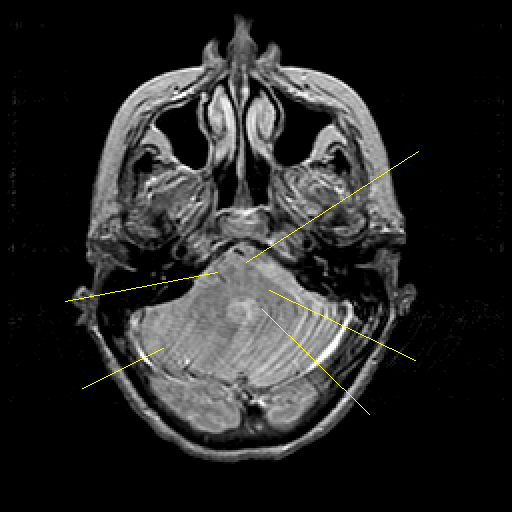

Proton density-weighted structural MR: Slice 13

Pointers